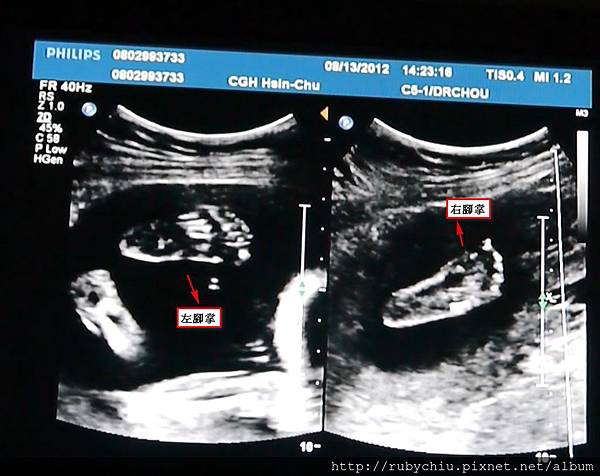

這張~左右腳丫特寫!5根腳指頭都有~~ 小腳丫好cute喔!